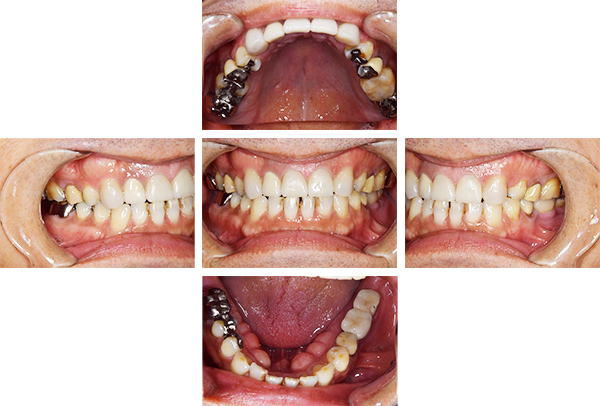

インレー・クラウン・インプラント症例

治療前

治療後

治療期間 16回(8ヶ月)

費用 ・インプラント(FCZ)1本

・セラミックインレー6本

・オールセラミックプレミアムクラウン6本

・FCZ6本

合計:2,552,000円

治療リスク・副作用 ・詰め物、被せ物をする時は自分の歯を削ることになります

・歯ぎしり・食いしばりが強い方は、セラミックが割れてしまうことがあります。